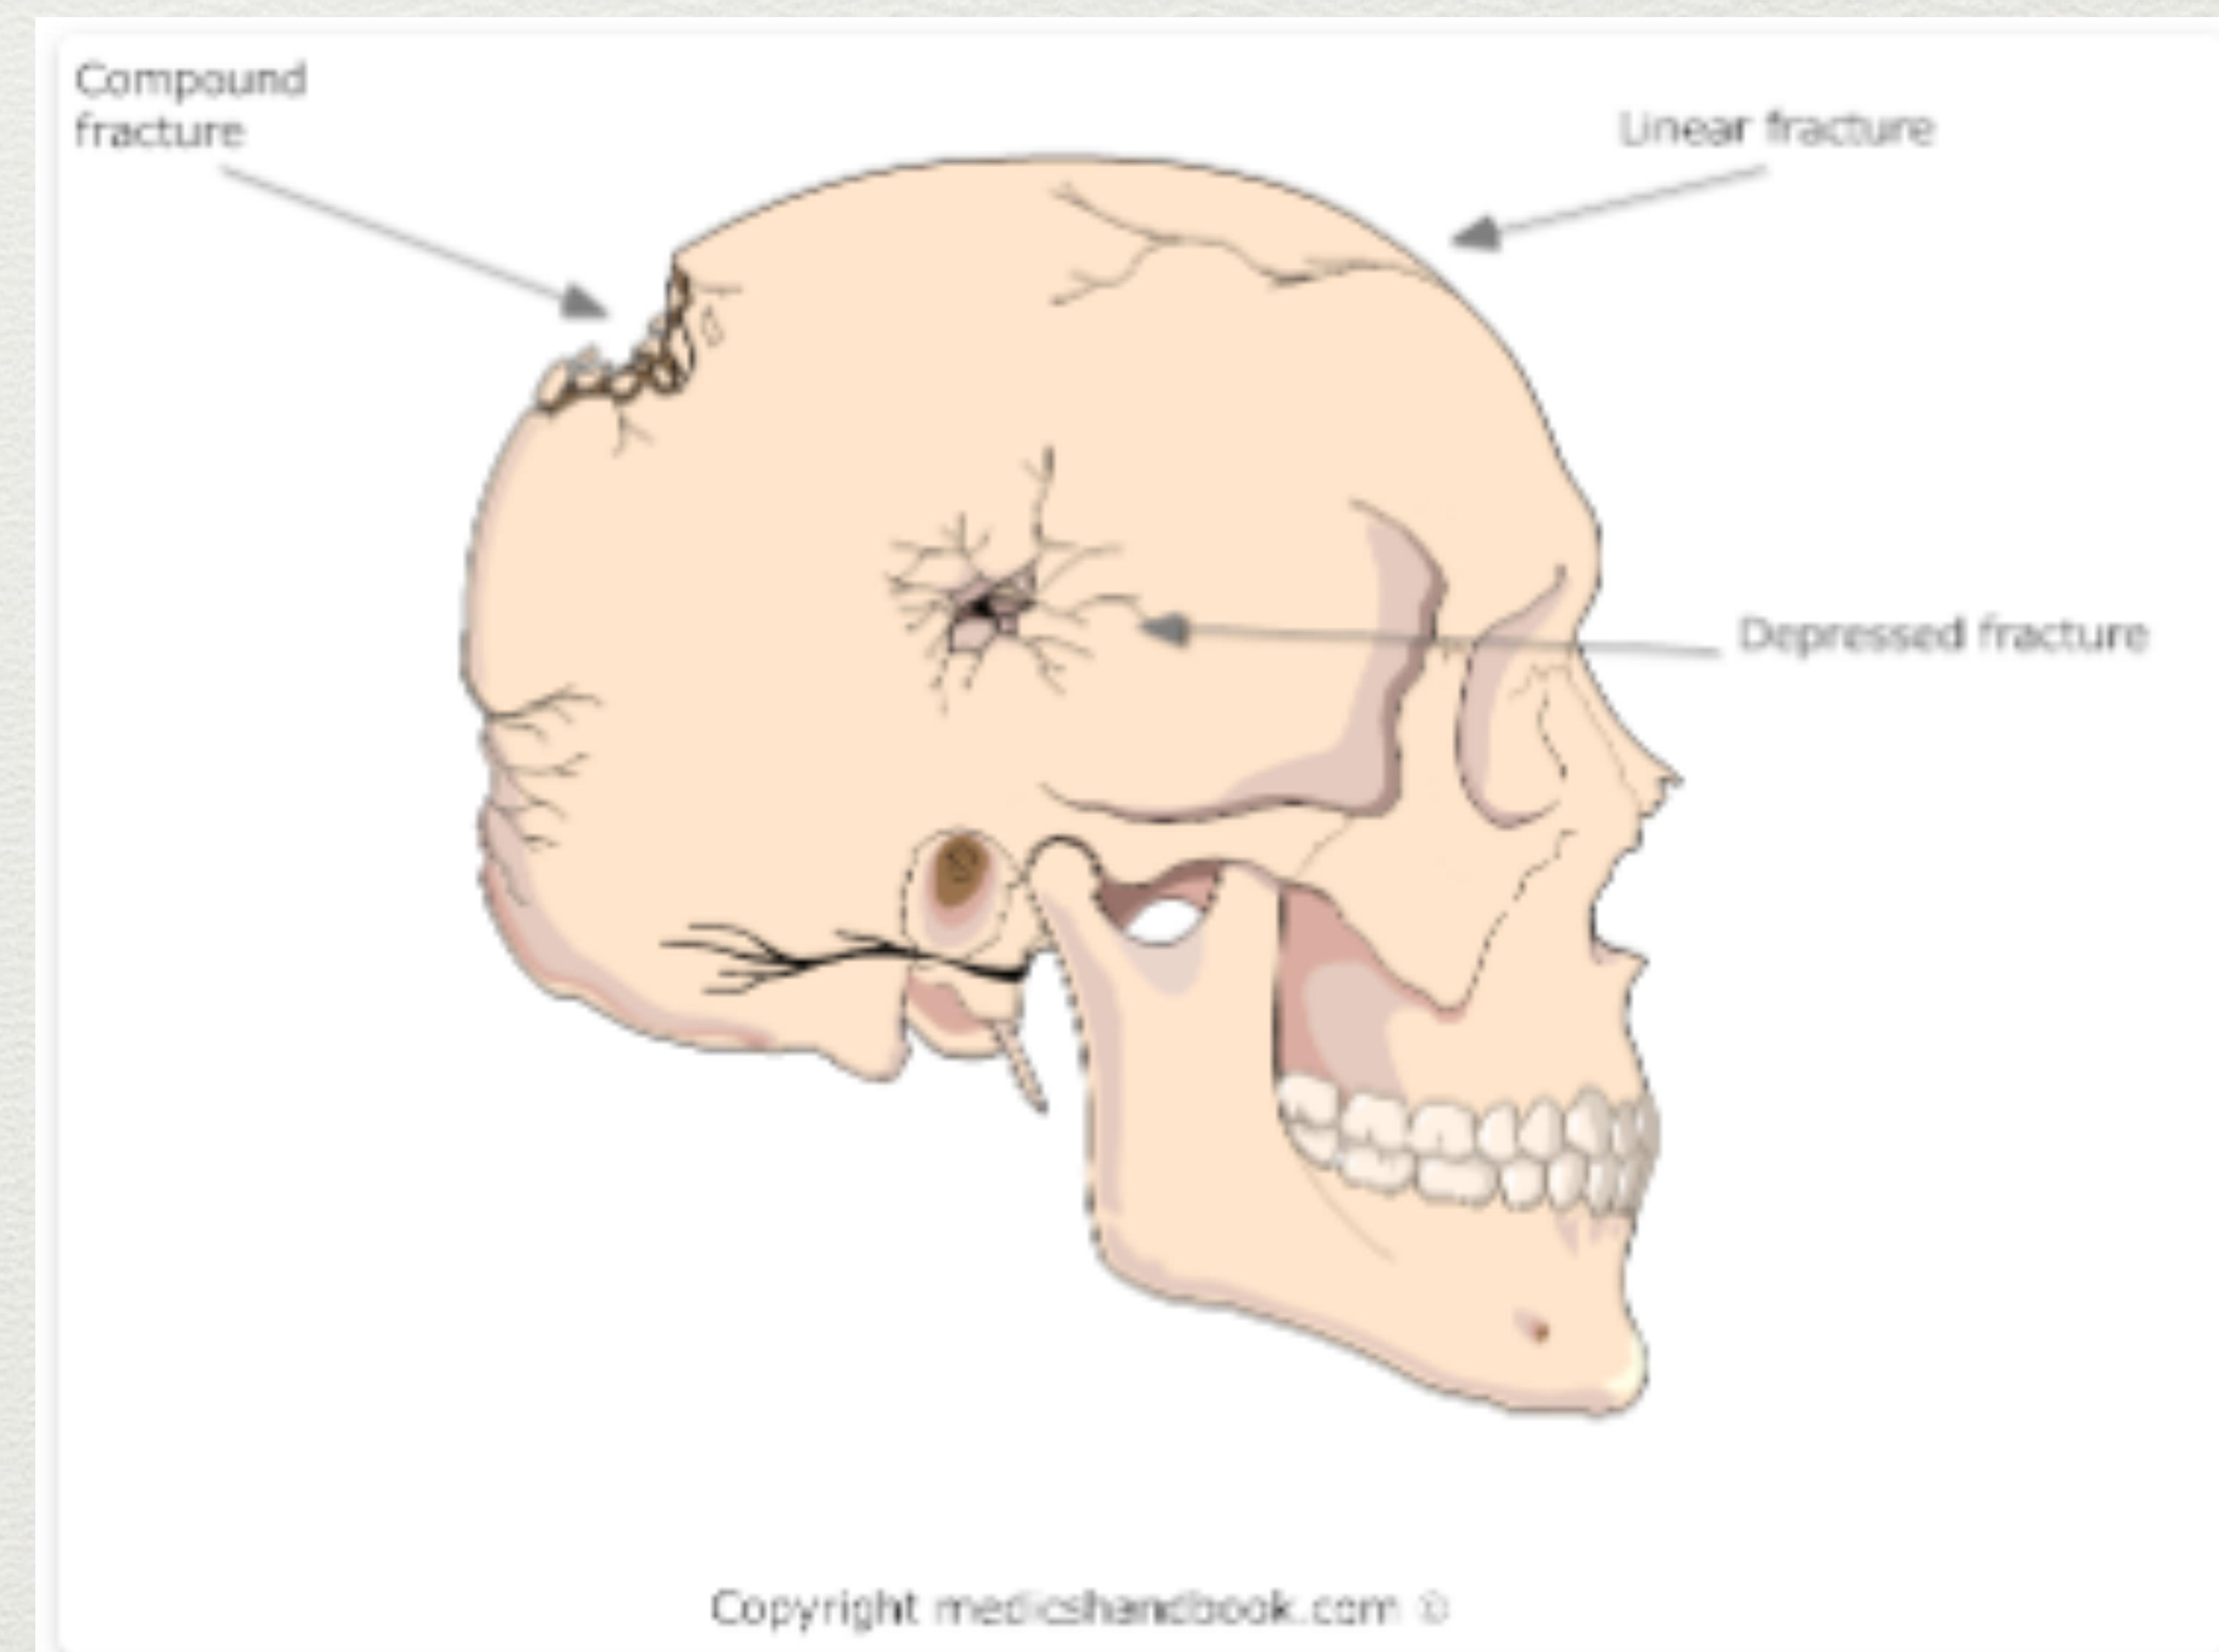

Skull Fracture

- From contact force.

- Usually associated with a brief loss of consciousness.

- Linear: Lateral convexities of skull.

- Depressed: Blunt force from an object with a small surface area (e.g., hammer).

- Compound fracture: Open fracture.

- Basal Skull Fracture (BOS): Severe blunt trauma to forehead or occiput.

Diagram illustrating types of skull fractures.